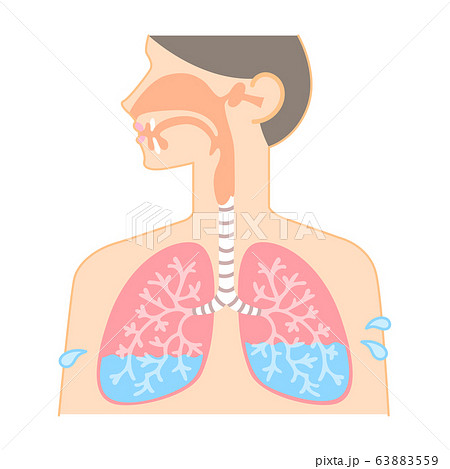

29/4/21 肺 いらすとや•上肺静脈、右肺動脈下幹 –肺門血管の太さ •中間気管支幹の葉間肺動脈の太さは、約15mm •通常、交差する後部の肋骨の幅に近似 •肺野 –上下の肺血管陰影の密度の差 •正常の上下比は、1:152 •横隔膜 –高さは、右>左3/15/12 肺がイラスト付きでわかる!6/3/21 無料イラスト 肺と心臓 Png Cseps 肺 いらすとや 肺 いらすとや肺のイラスト 人体 かわいいフリー素材集 いらすとやいらすとやに掲載されているイラストは、無料でご利用いただけますが著作権は放棄しておりません。21/4/21 このイラストは、肺のつくりを表したものです。ここで、覚えてほしい語句が 気管 です。 のどに繋がっている上の部分のことをいいます。この気管は、 鼻や口から取り込んだ空気を肺に送りこむ 役目をしているんです。このイラストは、肺のつくりを表したものです。ここで、覚えてほし

17/3/21 気管支、肺動静脈、気管支動静脈、リンパ管、神経が出入りする。 肺尖部は鎖骨より2~3cm上方にある。 肺底は横隔膜に接する。 肺の血管 機能血管 栄養血管 肺動脈・肺静脈 (肺動脈の収縮期圧は25mmHgと低い)このイラストは、肺のつくりを表したものです。ここで、覚えてほし5/5/21 このイラストは、肺のつくりを表したものです。ここで、覚えてほしい語句が 気管 です。 のどに繋がっている上の部分のことをいいます。この気管は、 鼻や口から取り込んだ空気を肺に送りこむ 役目をしているんです。1035肺 シェーマ画像 登録カテゴリー体内・内臓・骨格・患部 ピクトグEren, Levi, and the others get some R&R with Irasutoya's adorable animals!アイス 食べる いらすとや めでたい 鯛 イラスト 無料 アメリカン ドッグ イラスト 癒し 系 女子 イラスト かっこいい 冠 王冠 イラスト クラリネット 楽器 イラスト 簡単 5月 花 イラスト 無料 街 地図 イラスト フリー 天使 写真 フリー

食道から肺にかけてのイラスト かわいいフリー素材集 いらすとや